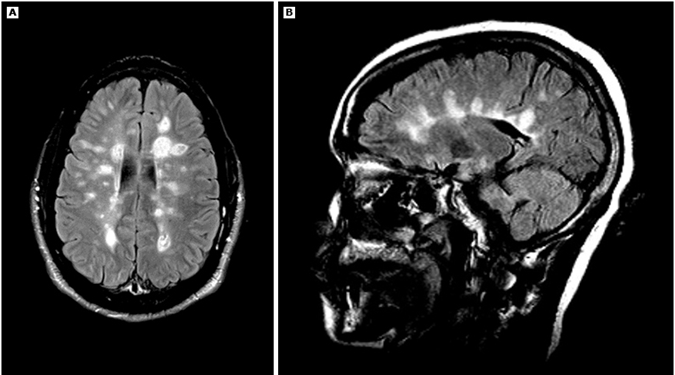

Очаги на МРТ, характерные для РС, обычно выявляются в перивентрикулярных областях, мозолистом теле, семиовальном центре и, реже, в структурах подкоркового белого вещества и подкорковых ядрах. Очаги РС (бляшки) обычно овальной формы. Очаги, как правило, распространяются от мозолистого тела под прямым углом; при оценке изображений на сагиттальных срезах, такой характер изменений называется пальцы Доусона. Очаги РС имеют повышенную интенсивность на протонной плотности и T2-взвешенных изображениях. Многие очаги, особенно которые отмечаются длительно, гипоинтенсивные на T1-взвешенных изображениях (так называемые, «чёрные дыры»); другие становятся совсем неразличимыми.

Аксиальные (A) и сагиттальные срезы (B) МРТ (FLAIR) головного мозга, на которых видны множественные овоидные перивентрикулярные очаги (пальцы Доусона) у пациента с рассеянным склерозом.